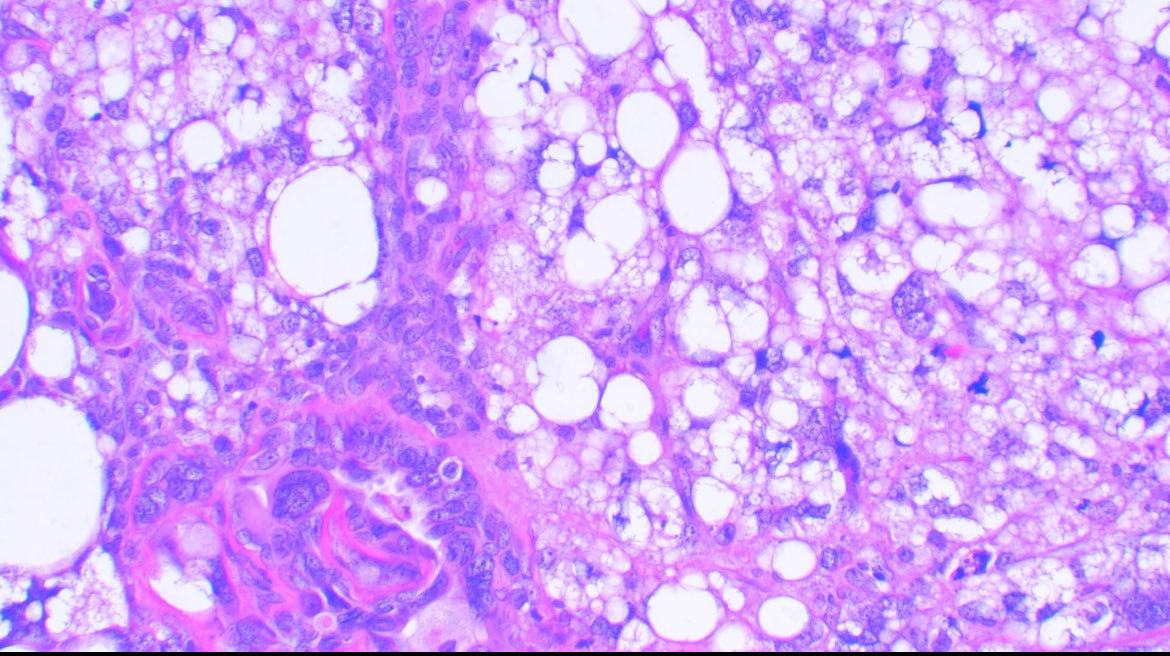

Uterine carcinosarcoma showing serous epithelial carcinoma and liposarcomatous heterologous element 🧐🧐 #Gynecology #WomensHealth #medicine #path #pathology